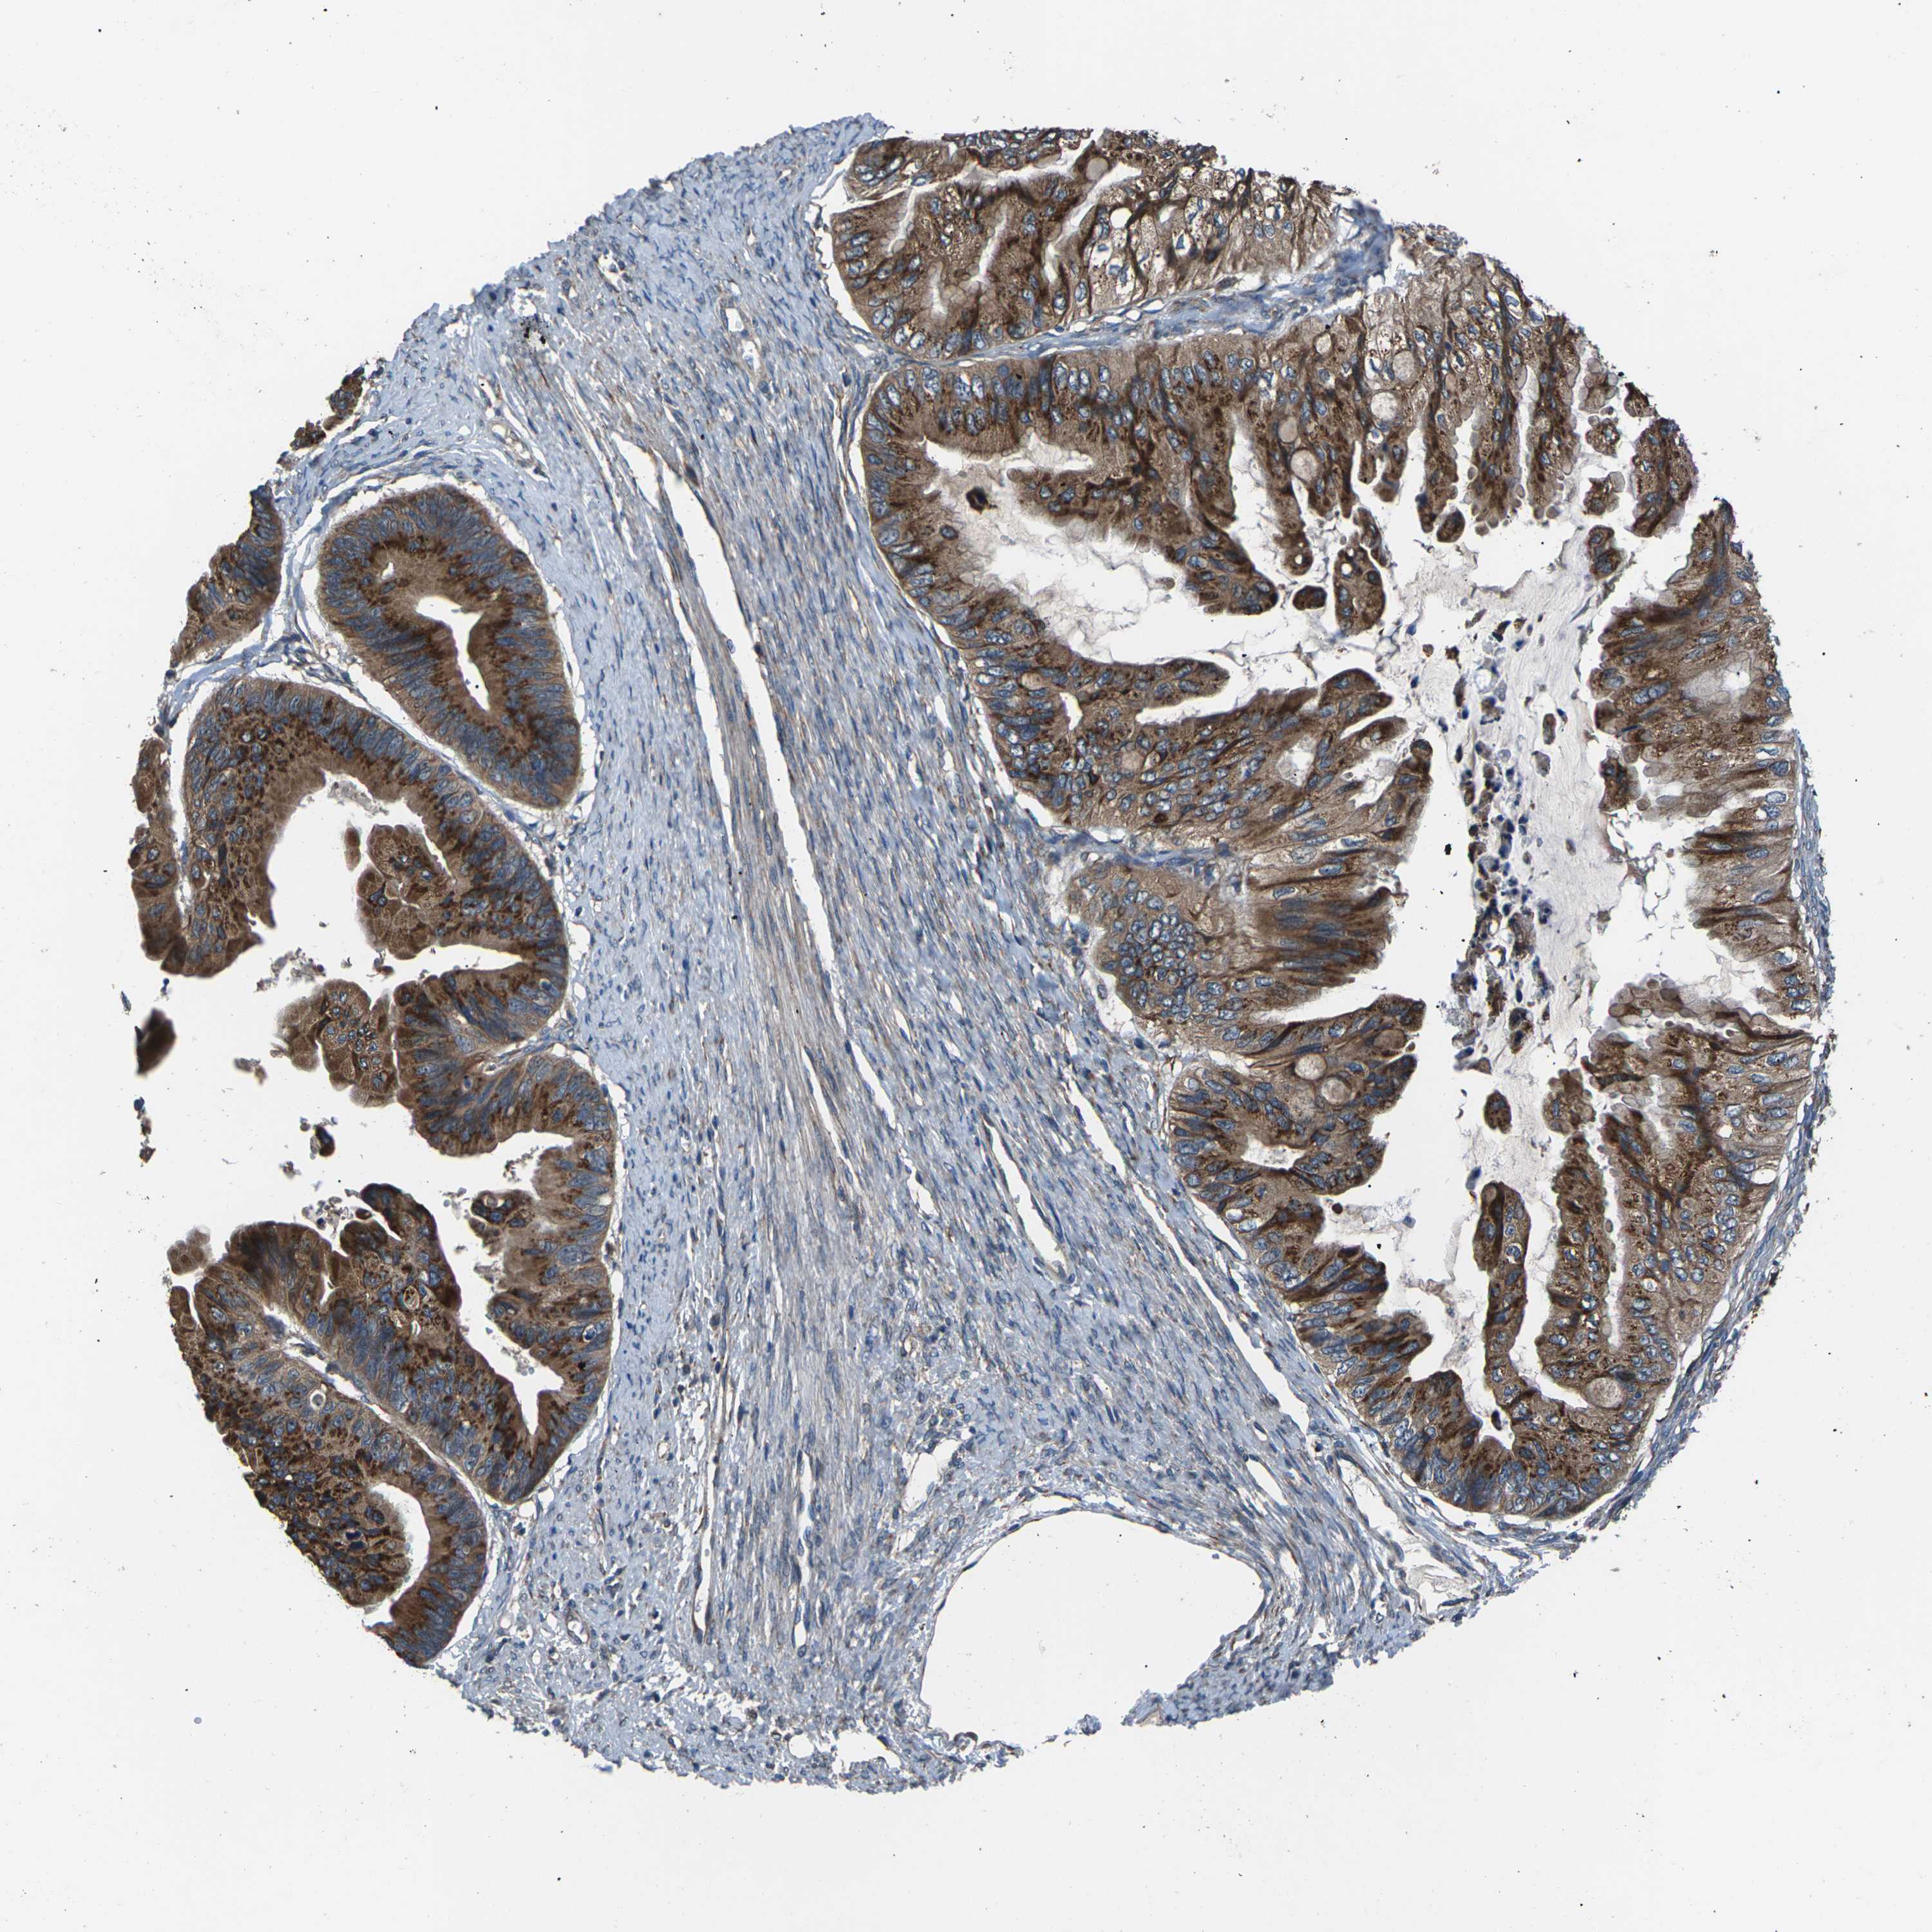

OVARIAN CANCER - Protein expressioni

A mouse-over function shows sample information and annotation data. Click on an image to view it in a full screen mode. Samples can be filtered based on level of antibody staining by selecting one or several of the following categories: high, medium, low and not detected. The assay and annotation is described here.

Note that samples used for immunohistochemistry by the Human Protein Atlas do not correspond to samples in the TCGA dataset.

Antibody stainingi

Antibody staining in the annotated cell types in the current human tissue is reported as not detected, low, medium, or high, based on conventional immunohistochemistry profiling in selected tissues. This score is based on the combination of the staining intensity and fraction of stained cells.

Each image is clickable and will lead to virtual microscopy that enables deeper exploration of all samples and also displays staining intensity scores, fraction scores and subcellular localization as well as patient and tissue information for each sample.

Antibody CAB014883

Staining

High

Medium

Low

Not detected

Intensity

Strong

Moderate

Weak

Negative

Quantity

>75%

75%-25%

<25%

None

Location

Nuclear

Cytoplasmic/membranous

Cytoplasmic/membranous,nuclear

Cystadenocarcinoma, serous, NOS

Carcinoma, endometroid

Cystadenocarcinoma, mucinous, NOS

Carcinoma, NOS